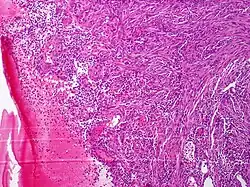

Włókniakomięsak – obraz mikroskopowy | |

Makroskopowo jest to biała lub jasnobrązowa masa o różnej twardości w zależności od zawartości kolagenu. Może być okrągłym lub guzkowatym guzem. Małe zmiany mogą być częściowo lub całkowicie otorbione, większe guzy są mniej odgraniczone i często rozciągają się jako wieloogniskowe zmiany w otaczających tkankach lub wzrastają w sposób rozlanie naciekający lub niszczący sąsiednie struktury[13]. W guzach o wysokim stopniu złośliwości widoczne są krwotoki i obszary martwicy. Mikroskopowo guz jest zbudowany z wrzecionowatych komórek o niewielkich różnicach w wielkości i kształcie, o ubogiej cytoplazmie i niewyraźnych granicach komórek wplecionych we włókna kolagenowe o równoległym wzorze[13].

Złośliwość histologiczna (grade) jest ustalana za pomocą oceny komórkowości, zróżnicowania, indeksu mitotycznego i obecności martwicy. Włókniakomięsak o niskiej złośliwości histologicznej (wysoko zróżnicowany) charakteryzuje się obecnością jednolitych, uporządkowanych komórek w obfitej ilości kolagenu. Czasem komórki są ułożone na wzór jodełki lub szewronu[11], a w pozostałych przypadkach są ułożone w grube sznury[13]. W guzach o wysokiej złośliwości komórki są bardziej upakowane, o mniejszych wymiarach i okrągłym kształcie, otoczone mniejszą ilością kolagenu. Jodełkowaty wzór ułożenia nie jest widoczny. Jądra komórkowe są pleomorficzne, widać liczne figury mitotyczne. Obecne są ogniska martwicy i krwotoków[13].